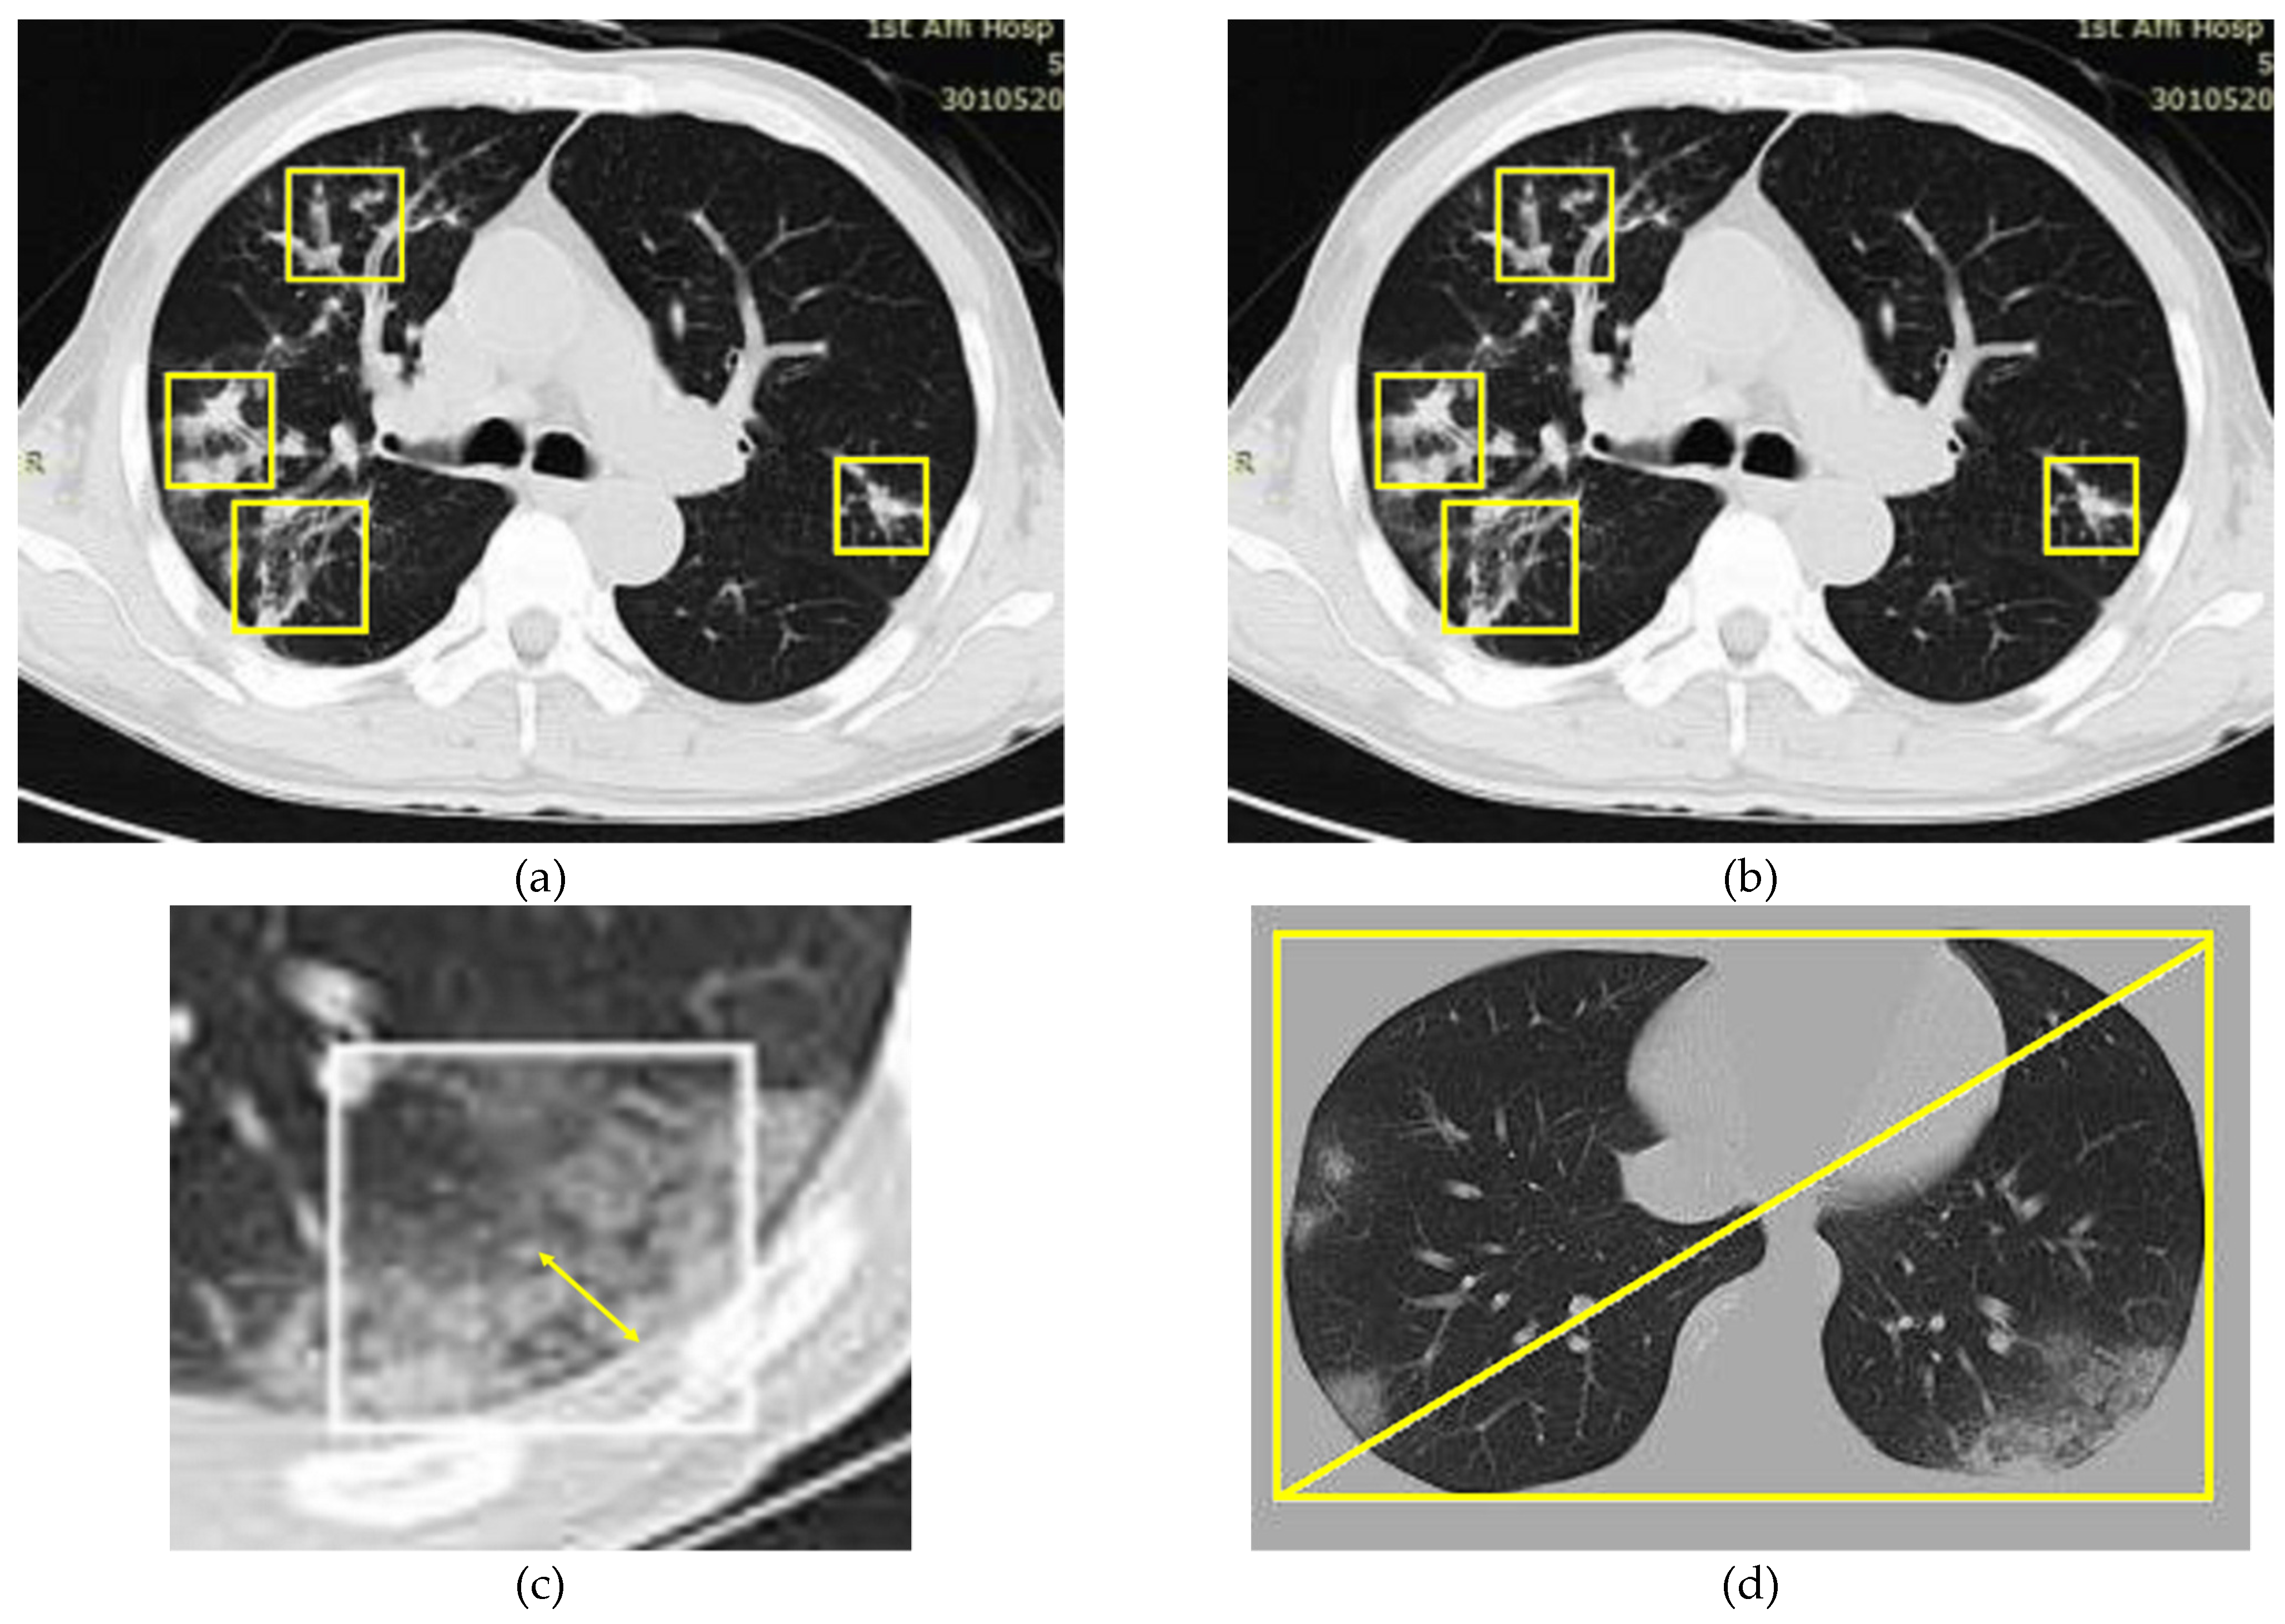

- Calculate the shortest separation from the mask for the middle of this classification (the double head arrow displayed in Figure 4c).

- A rectangular shape with minimum diagonal length is obtained from the target image (as shown in Figure 4d).

- Then, the normal area from the covered edge at that point is obtained from the distance estimated from step 1 numerically divided by the inclination of step 2).